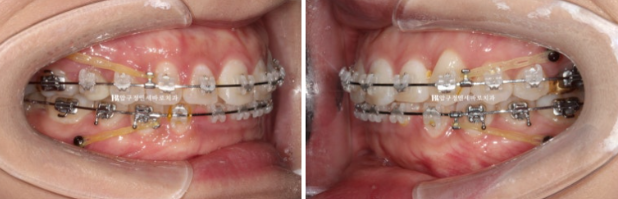

24.03

치료시작 11개월째 모습입니다.

미니스크류를 심고 전체 치열을 사랑니 공간으로 밀어내는 중입니다.

23.04~24.10

원래 좋았던 어금니 교합은 잘 유지가 되었습니다.